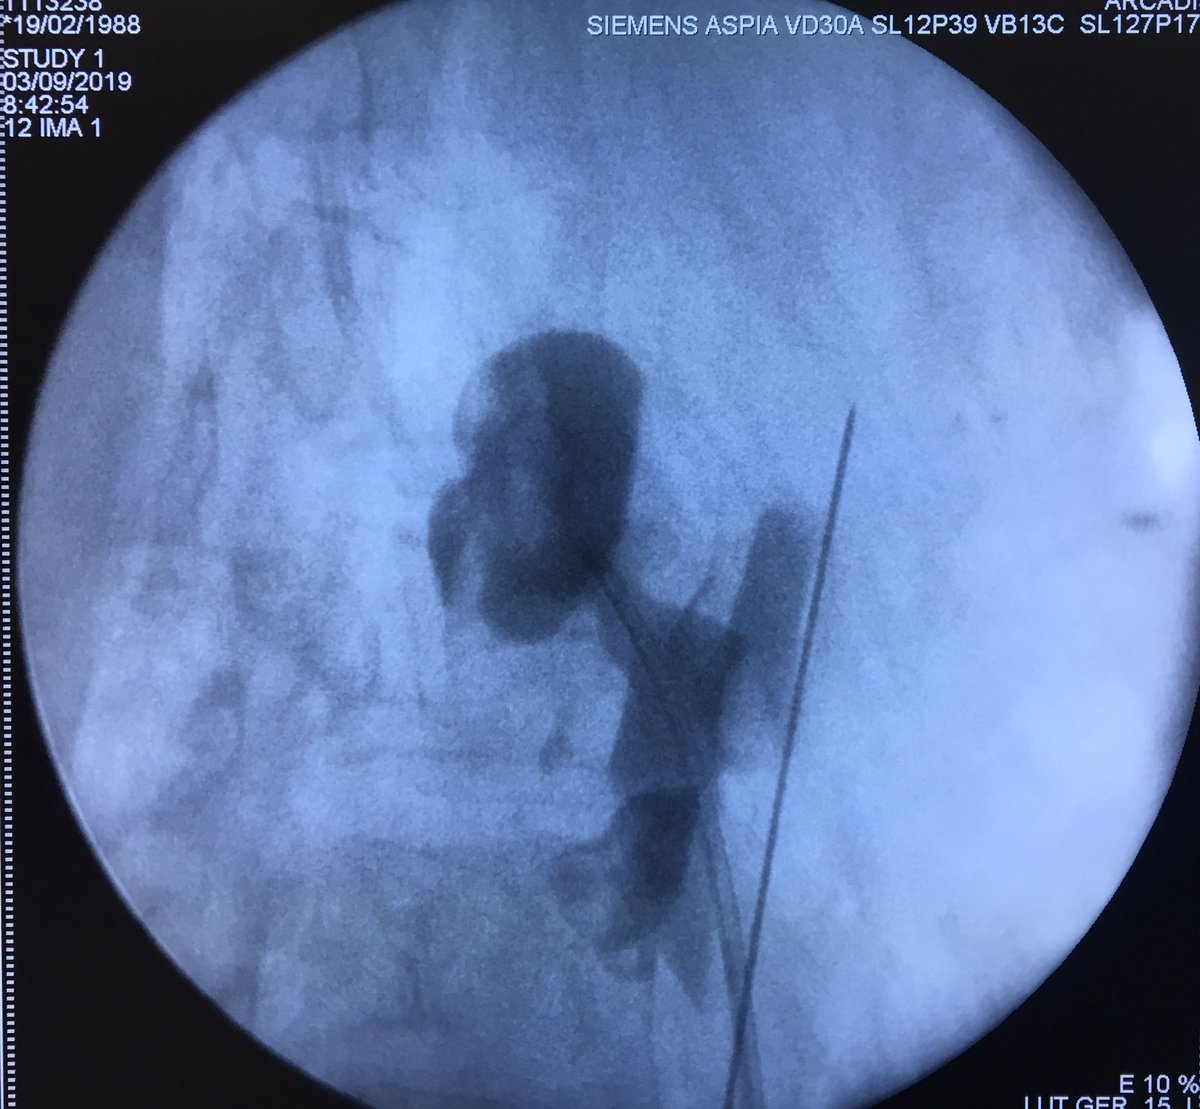

ECIRS with the Escovar-Leon Technique. Fast and accurate renal puncture! @urobraulio

#miniperc is a great option for aditional tract when flexible ureteroscope is not available for ECIRS. Triangulation with Escovar-León technique. #UroSoMe #Ilovepcnl @urobraulio @2fabiosepulveda